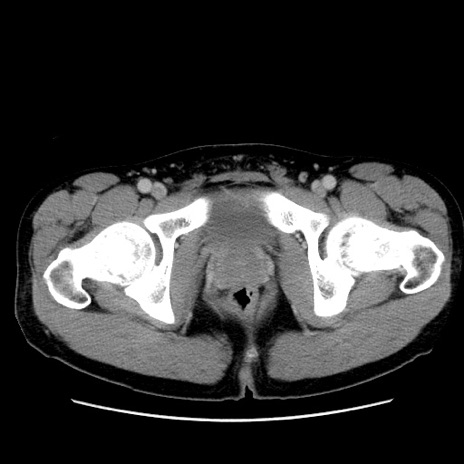

冠状断像

【症例】20歳代 男性

【主訴】心窩部痛

【現病歴】今朝より上腹部痛あり。一旦軽快していたが再度出現したため救急要請。昨日夕に白身の魚を含む刺身を食べた。

【身体所見】BP 136/89mmHg、HR 74/min、BT 37.0℃、腹部:膨満、軟、心窩部に圧痛あり。反跳痛なし、筋性防御なし、腸雑音やや亢進あり。

【データ】WBC 17700、CRP 0.48